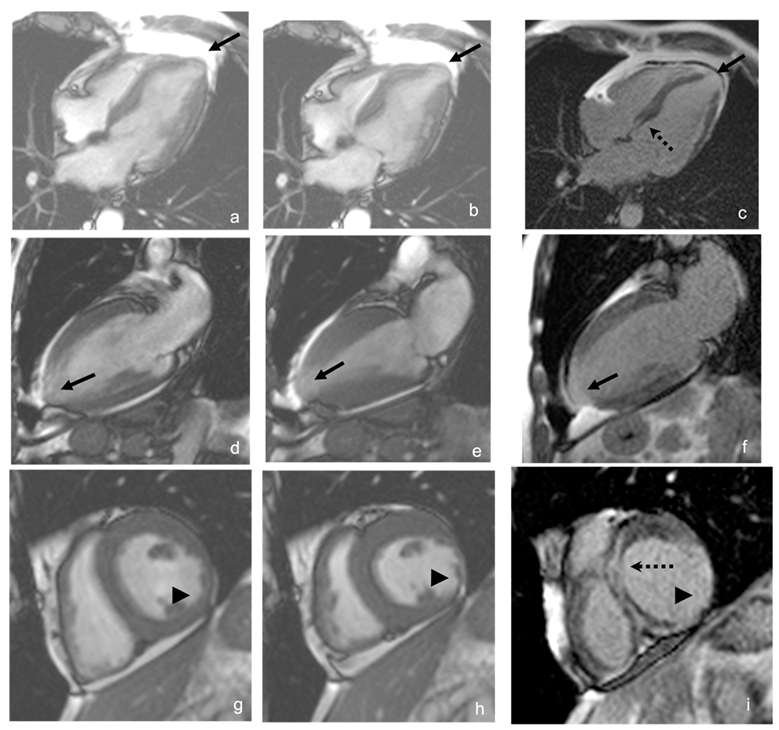

6.4. Cardiac Magnetic Resonance (CMR) Imaging

CMR makes it possible to identify myocardial fibrosis using late gadolinium uptake as a contrast agent [125]. Up to 20% of asymptomatic chronic-stage patients without LV segmental motion abnormalities have signs of fibrosis due to CMR.

The extent of myocardial fibrosis correlates with the severity of LV systolic dysfunction and the occurrence of ventricular arrhythmias [124]. Late gadolinium enhancement (LGE) can be transmural (44%), intramyocardial (32%), subendocardial (11%), epicardial (11%), or subepicardial [70]. The most frequently affected areas are the inferolateral wall and the apex (Figure 8). Transmural enhancement of two or more segments is a strong predictor of ventricular arrhythmias independent of other factors such as LVEF, age, gender, and extent of fibrosis. The extent of myocardial fibrosis has the potential to become an indication for implantable cardioverter defibrillator (ICD) in patients with CCC [122].

CMR offers advantages over echocardiography in the morphological and functional evaluation of the LV and RV because it is a tool with high spatial resolution, and the determination of volumes (LVEF/RVEF) does not depend on geometric assumptions [126]; it is also the best noninvasive tool for the evaluation of myocardial fibrosis or necrosis [127] and offers timely detection of RV systolic dysfunction in those patients in whom systolic dysfunction is not LV-dependent or when CC is not defined by clinical criteria [128]. Up to 3% of patients have LV apical aneurysms not detected by echocardiography [71,124]. However, the sometimes limited access to CMR preserves echocardiography as the initial and follow-up study of choice [124].